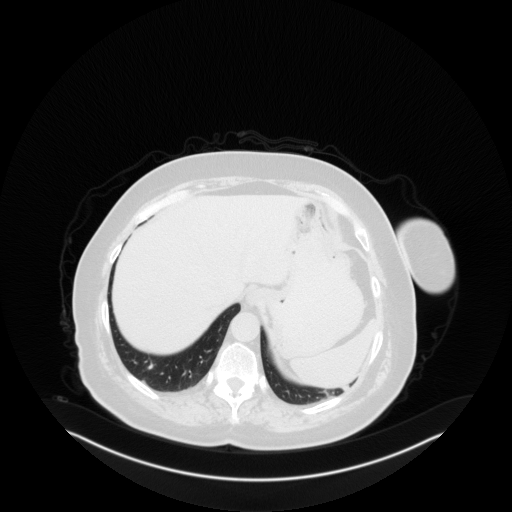

Image Grid

4Γ—3 grid: Rows show different image types (Original NATIVE, Reconstructed NATIVE, Original VENOUS, Generated VENOUS), Columns show windowing techniques (No Window, Lung Window, Mediastinum Window)

Original NATIVE CT scan (input)

Full window (WL 1023.5, WW 4095 β†’ Low βˆ’1024, High +3071)

Generated VENOUS CT scan (A→B translation)